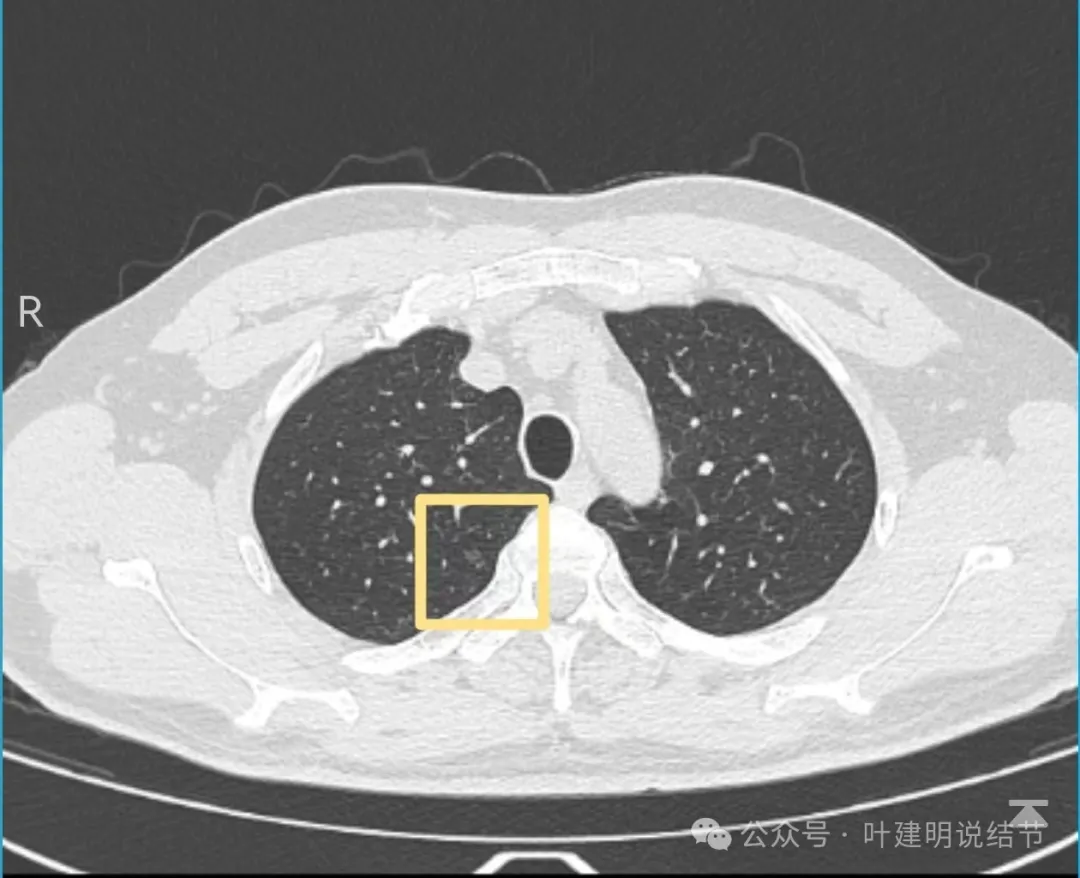

患者于1个月余前查体发现肺结节,无发热,无胸痛胸闷,无头晕头痛,无腹痛腹胀,于2024.04.26就诊于医院行胸部CT检查示脑两肺多发磨玻璃结节,左下肺后基底段达Lung-rads4B类,微浸润腺癌可能,建议手术干预。今为求进一步诊疗来诊。

左下叶结节,轮廓稍显模糊,邻近有血管走行,无血管弯征,病灶中间密度稍低,结节密度很淡,仅小片状模糊影似的。

右上叶与左下叶这两处结节均密度很低,非常淡,而且瘤肺边界并不是特别清晰,考虑少许肺泡上皮增生可能性大,目前没有什么风险,可常规年度复查随访。不能太着急,也不必太着急干预处理。我一直强调不要管最后病理是什么,而是从影像上判断风险如何、纯不纯,密度高不高,还能不能观察。你这种不单密度低,还小,不需要过分担心的,安心随访便可。意见供参考!

病灶出现,显模糊。

上图层面轮廓较清,但密度很淡,似见血管走行,但靠左前方的似条状磨玻璃密度与血管连着的到底是血管分支还是结节的一部分,其实并不确切。如果其实是血管分支,那病灶与它之间就不是空泡。

病灶在此层整体边缘显糊,灶内有空泡似的,瘤肺边界欠清。

边缘不平,还是灶内多发小空泡?邻近血管与之紧贴,但血管无异常走行。病灶密度很低,显糊。

中间所谓空泡更像是细支气管扩张,内壁非常光滑且圆形。

病灶边缘区淡而模糊。

这个病灶会是微浸润性腺癌吗?当然没有病理诊断,我也不能说百分之百必不会,但这样的病灶已经风险大到必得尽快手术切除干预了吗?显然还早着呢:1、影像不是典型的结节状;2、边缘与轮廓模糊不清;3、灶内似有细支气管扩张(更容易是细支气管扩张伴少许周围炎或肺泡上皮增生);4、血管邻近走但无牵拉影响;5、没有实性成分,没有锐利毛刺,没有胸膜牵拉,没有血管进入,没有任何倾向风险性高的影像特点。我一直强调:肺结节是否要干预处理,不要纠结于最后病理是什么,而要看风险高低;而风险高低的最重要术前判断依据一是随访有无进展,二是有没有实性成分。只要没有肉眼可见的影像上的实性成分,风险就是低的!何况病理也是人看的,原位还是微浸润,不典型增生还是原位有时也在一念之间。